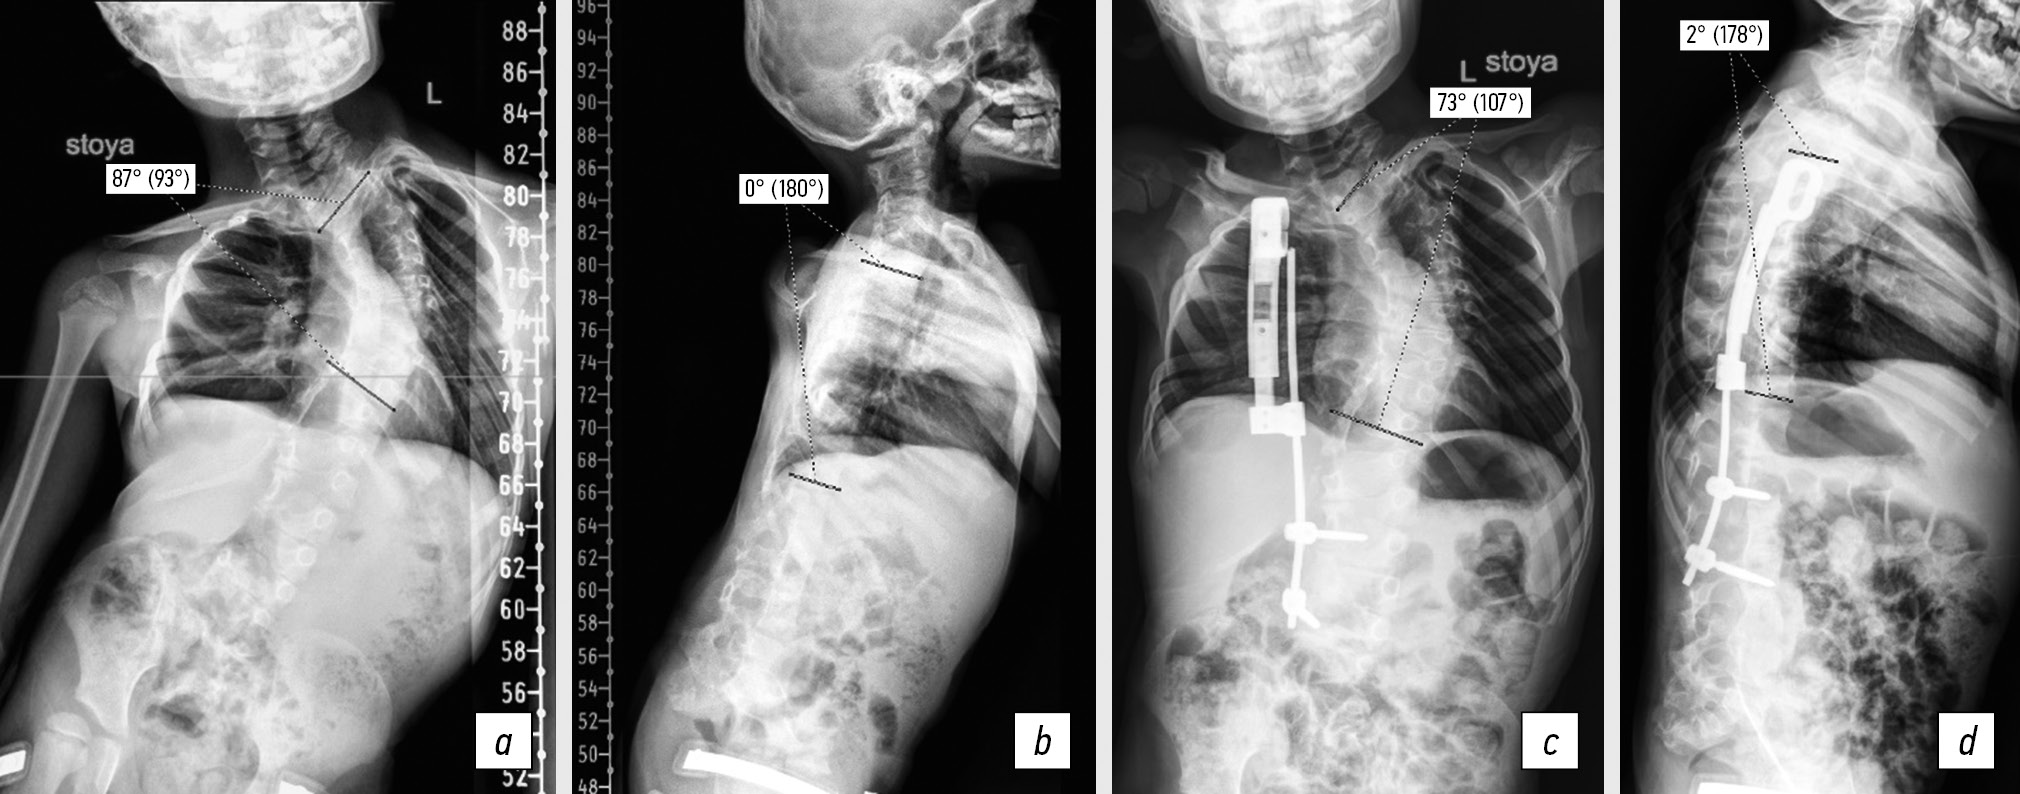

As in primary surgical correction, indications for staged surgical treatment were severe congenital deformity of the spine and/or rapid progression of curvature (>10° per year), TIS progression, pathological kyphosis in the thoracic spine, and pathological lordosis (Fig. 3). In the case of correction loss and hardware destabilization, staged surgical treatment aimed at restoring the hardware stability was also performed.

Fig. 3. Panoramic radiograph of the spine in frontal and lateral projections before and after the surgical treatment. Patient, 6 years old: a, b, scoliosis before the surgery (87°), lordosis of the thoracic spine (0°); c, d, scoliosis after the surgery (73°), kyphosis (2°)

The spinal deformity apex was localized at the level of the vertebrae from ThIII to ThX and corresponded to the middle spinal motion segment involved in the nonsegmented nail. The median number of vertebrae in a nonsegmented nail was 4 (IQR 3). Costal synostosis included fusion of four ribs on average (minimum, 3; maximum, 12). An equal number of patients had left-sided and right-sided localizations of curvature arcs.

The average value of scoliotic deformity in the study patients was 74° (IQR 22.75). The patients with scoliotic deformity had hypokyphosis reaching an average of 15° (IQR 32°), whereas some patients had pathological lordosis of the thoracic spine up to 20°.